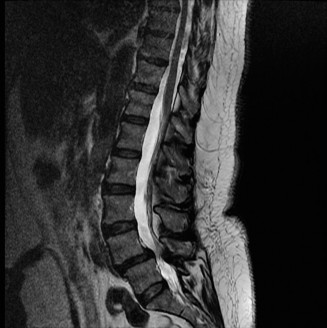

To evaluate the neural elements and the soft tissue structures, a comprehensive MRI of the lumbar spine without contrast was obtained. The T2-weighted sagittal and axial sequences confirmed the Grade 2 anterolisthesis and demonstrated severe bilateral foraminal stenosis at L5-S1. The exiting L5 nerve roots were severely compressed between the hypertrophied, fibrocartilaginous pseudarthrosis tissue of the pars defect dorsally, and the bulging, degenerated L5-S1 disc and superior endplate of S1 ventrally. Furthermore, the MRI revealed Modic Type II changes (fatty replacement of the subchondral bone marrow) in the adjacent vertebral endplates, confirming chronic biomechanical stress and discogenic degeneration. The central canal remained relatively patent, which is characteristic of isthmic spondylolisthesis, as the posterior neural arch is left behind during the anterior translation of the vertebral body.